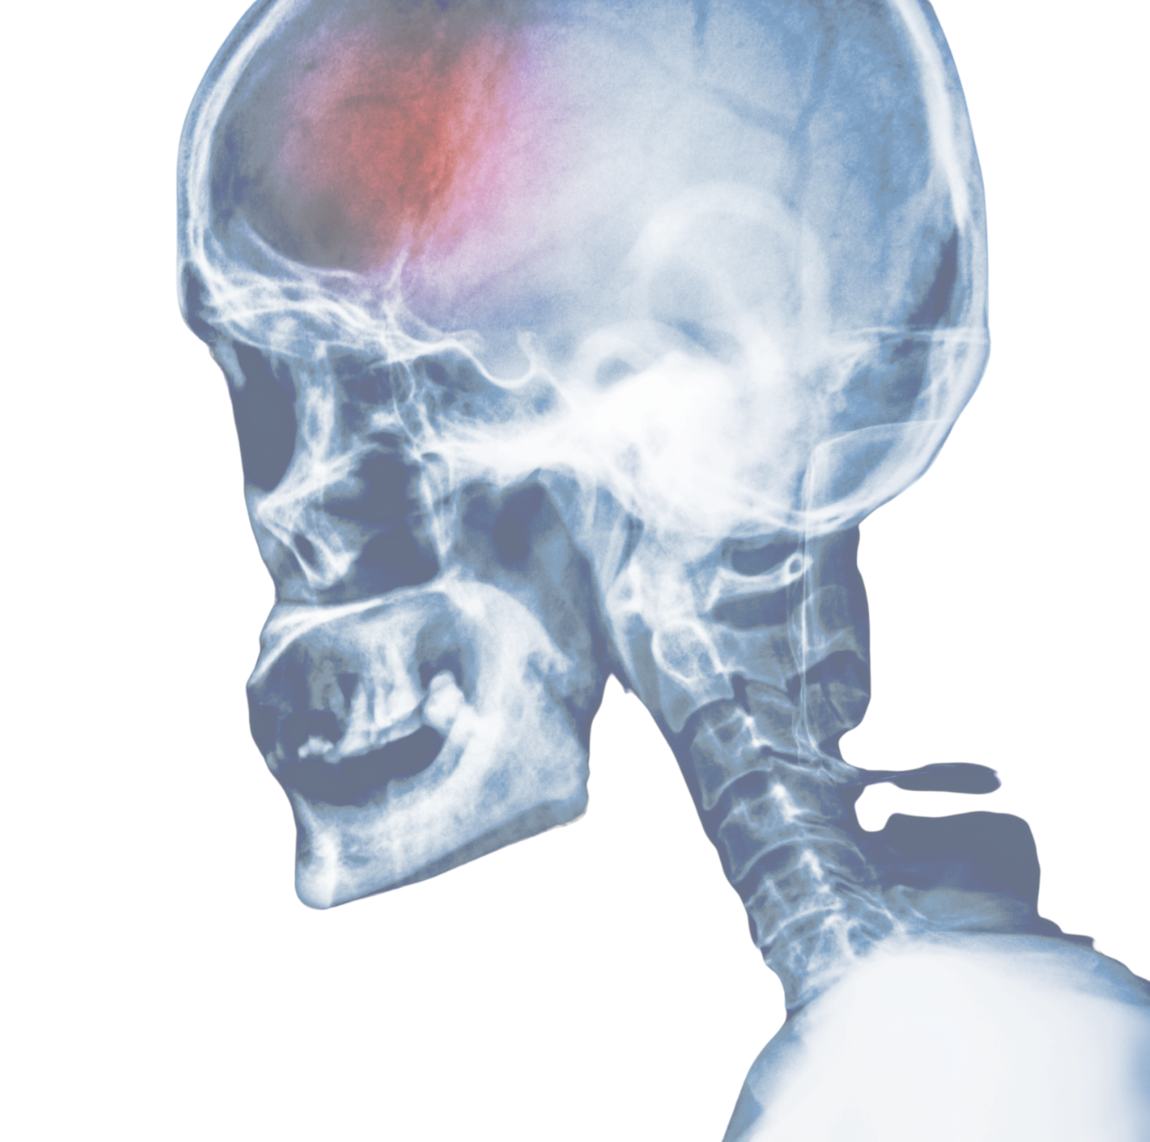

| James (1:16) | Yeah absolutely. So I came across a research project that you produced called Too Many to Count and I will say to listeners it's not an easy read.It's about brain injury from domestic abuse and can you give us the sort of headline stats, the things that made me go “what? Surely not” like that on my screen. |

| Steffy (1:38) | Yeah absolutely and you're completely correct to sort of give people a bit of a heads up around the content. It isn’t easy reading I think even for people who have worked in this space for a long time the statistics are still quite shocking.So what we found from our study looking at brain injury in the context of domestic abuse was that as many as one in two survivors of domestic abuse could be living with a potential brain injury and obviously as people who listen to this podcast and yourself you know you're well aware brain injury can present in lots of different ways which is one of the reasons that this hasn't really been understood fully before and why this research is so important. So one in two people potentially living with a brain injury and many of those people have experienced potential mechanisms for brain injury through domestic abuse particularly physical violence so thinking about hits to the head neck and face and non-fatal strangulation both potential mechanisms and obviously the more that those things happen, and these things seldom happen as a one-off incident, the more that these things happen the higher the risk is that someone could potentially live with a brain injury as a consequence of what they've experienced. So it's hard reading but it's a harsher reality for those who may know they're living with a brain injury but most people don't because of how it presents and because of the lack of education and awareness around this in this particular context and that's you know not anyone's fault that the conversation is still emerging the research is still you know very new particularly here in the UK but that may be the headline is one in two. |